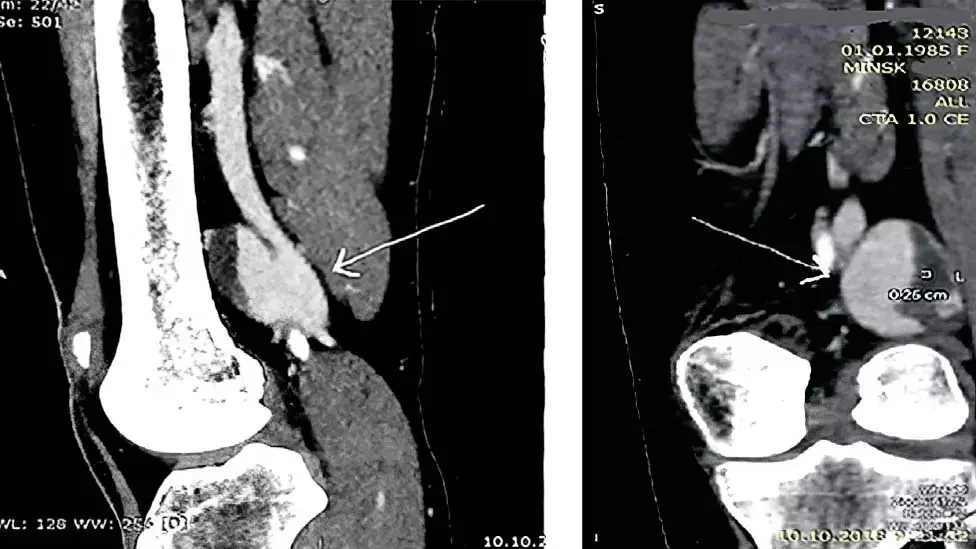

Женщина, 33 года, попадает по скорой медицинской помощи в реанимацию одного из стационаров Минска с клинической картиной fs444s668f66fРисунок 2. КТ-флебография с разных ракурсов детализирует хирургическую анатомию аневризмы.тромбоэмболии легочной артерии. Симптомы: выраженная одышка, слабость, чувство нехватки воздуха, тяжесть в области шеи, першение в горле. Тромбоэмболия подтверждена, проводится тромболизис, пациентке назначается антикоагулянтная терапия.

В ходе гематологического обследования выявлена гетерозиготная тромбофилия, ассоциированная с высоким уровнем VIII фактора свертывания крови и наследственным дефицитом XII фактора свертывания крови со вторичной недостаточностью фибринолиза. Во время третьей госпитализации по поводу рецидива ТЭЛА в ходе выполнения ультразвукового исследования вен нижних конечностей пациентка из положения лежа переводится в ортостаз и выявляется мешковидная аневризма подколенной вены с грибовидным выступом 29×34 мм (лежа — 15 мм) с пристеночным тромбообразованием. Дообследуют пациентку с помощью КТ-флебографии, которая детализирует хирургическую анатомию аневризмы (см. рис. 2). Подтверждается пристеночный тромбоз аневризматического мешка.

— В качестве дополнительного метода диагностики (для выработки хирургического подхода, детализации патологии) используется КТ- или МР-ангиофлебография, — объясняет Иван Климчук. — Безусловным плюсом данного метода является возможность одномоментной оценки русла легочной артерии с целью подтверждения либо исключения ТЭЛА.